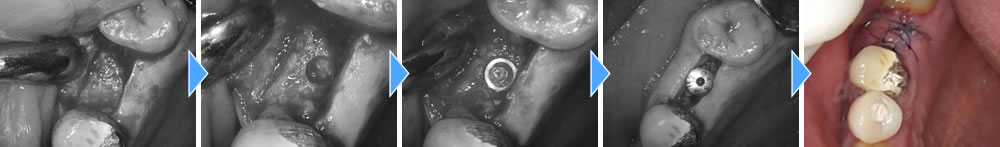

また、奥の歯はCT写真にて骨が弱っていたため、しっかりと歯茎を切開し、骨の状態を確認しながら施術を行っていきました。

手術後3ヵ月間は治癒期間を設け、しっかりと骨とオステオインテグレーションしている事を確認し、上部の歯を作成していきました。

結果、しっかりと噛む事ができ、審美的にも回復する事ができました。